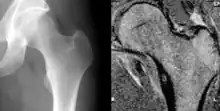

| Osteoid osteoma of the lesser trochanter: X-ray and MRI with marked sclerosis around the nidus | |

The most common symptom is pain that can be relieved with over the counter pain medication in the beginning. After the benign tumor develops further the pain can not be alleviated with medication and minor to severe swelling starts to occur. Although, in some cases the pain level remains the same for years, and regular NSAIDs intake keeps the pain at bay. The tumor is often found through x-ray imaging. Conventional radiographs reveal a well-demarcated lytic lesion (nidus) surrounded by a distinct zone of sclerosis that allow doctors to identify the tumor.[4]

Radiographs in osteoid osteoma typically show a round lucency, containing a dense sclerotic central nidus (the characteristic lesion in this kind of tumor) surrounded by sclerotic bone. The nidus is seldom larger than 1.5 cm.

The lesion can in most cases be detected on CT scan, bone scans and angiograms. Plain radiographs are not always diagnostic. MRI adds little to the CT findings which are useful for localisation. Radionuclide scanning shows intense uptake which is useful for localisation at surgery using a hand held detector, and for confirmation that the entire lesion has been removed.[8][9]